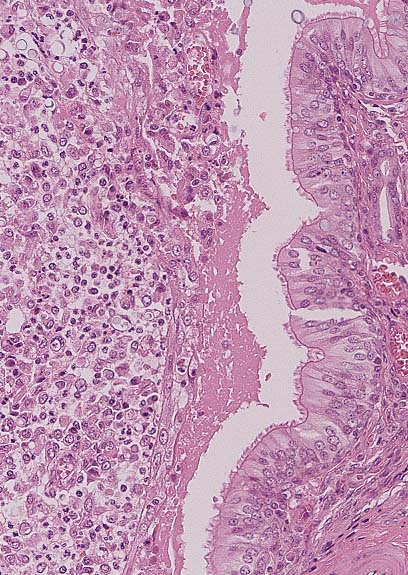

Neuronal vacuolation in the brain stem of a Suffolk ewe with scrapie. (HE, 100X, 61K)

Intraneuronal vacuole characteristic of scrapie in a 3-year-old a Suffolk ewe. (HE, 400X, 61K)

Contributor's Diagnosis and Comments: Brain stem: The sections of brain stem and spinal cord display cytoplasmic neuronal vacuolation.

AFIP Diagnosis: Brain stem: Neuronal vacuolation, multifocal, with mild astrocytosis, and multifocal axonal degeneration, Suffolk, ovine.

Conference Note: Scrapie is a disease with international scope and implications. It is a chronic disease involving the central nervous system of sheep and goats and has an incubation period of 1.5 to 5 years, depending on the age at exposure. Infection usually occurs around the time of birth, and probably via ingestion, but the possibility of vertical modes of transmission remains. The agent initially proliferates within the lymphoid tissues and lower intestine and may take up to 2 years to reach the central nervous system. A further 2 years may elapse before clinical symptoms appear. Early in the disease, animals are alert but excitable, and may have seizures. Later, paresthesia may develop, manifested as agitated rubbing against posts and trees and nibbling at feet and legs. There is progressive dysmetria, emaciation, and finally paralysis and death. Apart from self-trauma, there are no gross lesions, and no inflammatory changes. Histologically, the most characteristic finding is the presence of intraneuronal vacuoles in the CNS.